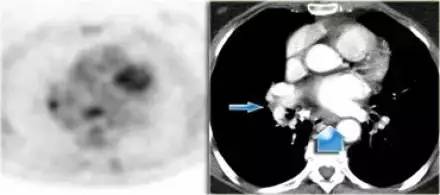

PET 图像,显示淋巴结 FDG 摄取增加,而同一横断面 CT 未显示淋巴结增大(蓝色箭头),该淋巴结癌症转移的可能性很高,PET 检查对不增大淋巴结的特异性高于增大的淋巴结。